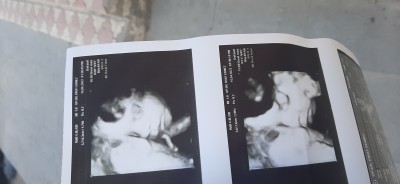

Hanımlar bugün kontrole gittim ve ilk kez bebeğimi net gördüm. Eşim sana benziyor diyor . Çok tuaf bi duygu insanın içinde bi canlı olması bugün de net görünce bi tuhaf oldum:)

Benim bebeğim . Bugün ilk defa net gördüm de . Sagolun tesekur ederim

Doktorum kıza benzetmişti canm. Bugün farklı doktora gittim göstermiyor dedi. 28 haftalık canm olduk